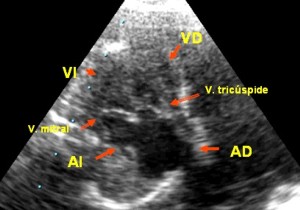

Síndrome del ventrículo izquierdo hipoplásico

(ver figura y video del ventrículo izquierdo hipoplásico haciendo clic aquí). En este caso la válvula tricúspide y el ventrículo derecho son normales, pero la válvula mitral no se ha perforado y en su lugar aparece una membrana fibrosa (atresia mitral) y el ventrículo izquierdo es tan pequeño que su cavidad apenas se identifica.

Cuatro Cámaras, ventrículo izquierdo hipoplásico